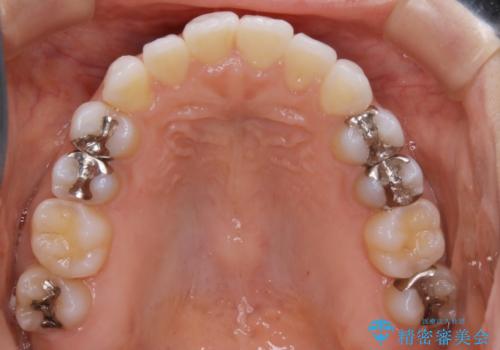

- 前歯のガタつき改善を主訴にご来院されました。

ガタつき自体は軽度で、奥歯の噛み合わせのズレもほとんどなかったため、非抜歯でマウスピース矯正装置を選択しました。

歯列の幅の拡大と歯を小さくする調整を行うことで並べるスペースの確保を行いました。この方法は、ガタつきをとりたいところに直接スペースを作ることができるので治療期間を短縮することができ効率的です。

歯列弓の拡大

歯並びが悪くなる原因の一つに「歯列弓の狭窄」というものがあります。

奥歯や前歯が内側(舌側)に倒れ込んでしまったり、歯が生えてくる位置が内側になってしまうことにより歯並びのアーチが狭くなってしまうことを言います。

このような場合、歯並びのアーチを拡大してあげるだけでもガタつきを無くすためのスペースがかなり作れることがあります。